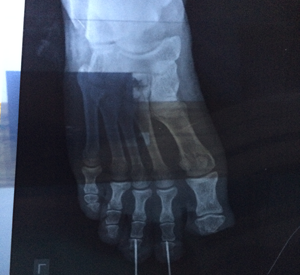

Trauma Surgery

Trauma surgery is a surgical specialty that utilizes both operative and non-operative management to treat traumatic injuries, typically in an acute setting.